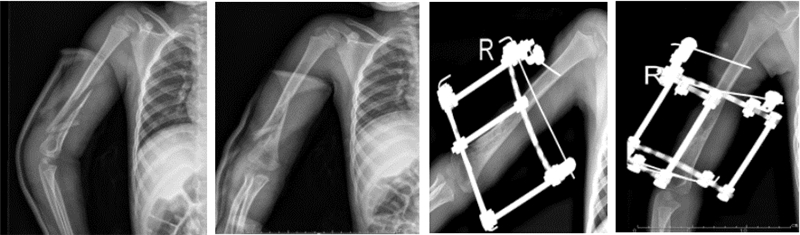

首先麻醉下手法整复骨折,C臂机透视确认骨折复位情况,主要观察骨折解剖力线恢复情况,然后根据复位结果确认下一步治疗措施。如果骨折基本复位或者只残留少许成角畸形,则开始行Ilizarov外固定治疗。固定时根据骨折粉碎情况以及骨折断端离上下关节面远近分别在骨折上下端各一个全环及半环或者两个全环固定。固定时先在远离骨折处上下各行两枚交叉全针,穿针时注意利用肌间隙进入,缓慢进针,局部生理盐水冲洗,减少对血管、神经的损伤,然后用一个全环固定。此时再次C臂机透视以确认骨折复位情况,然后根据骨折稳定性及骨折近远端软组织情况,决定是否再行一个全环或者半环固定(或两半针代替)。如果有粉碎骨折片明显远离解剖力线,则加用一枚橄榄针向力线处牵引后固定[1]。如果骨折闭合整复困难,则在畸形最为明显处行一小切口,然后在尽量不损伤骨膜的基础上整复骨折,再用闭合复位的技巧行Ilizarov外固定。手术结束时常规复查X线,了解骨折复位情况,如果仍有成角等畸形,则再次通过Ilizarov微调技术给予调整到骨折可接受的程度。术后3 d、10 d再次行影像学检查,根据骨折复位情况决定是否再次微调(图 1)。对于粉碎性骨折伴皮肤撕脱需要植皮者,在Ilizarov固定后可以多次清创植皮(图 2)。

图 2 Ilizarov外固定治疗6岁皮肤撕脱伴肱骨粉碎性骨折患儿